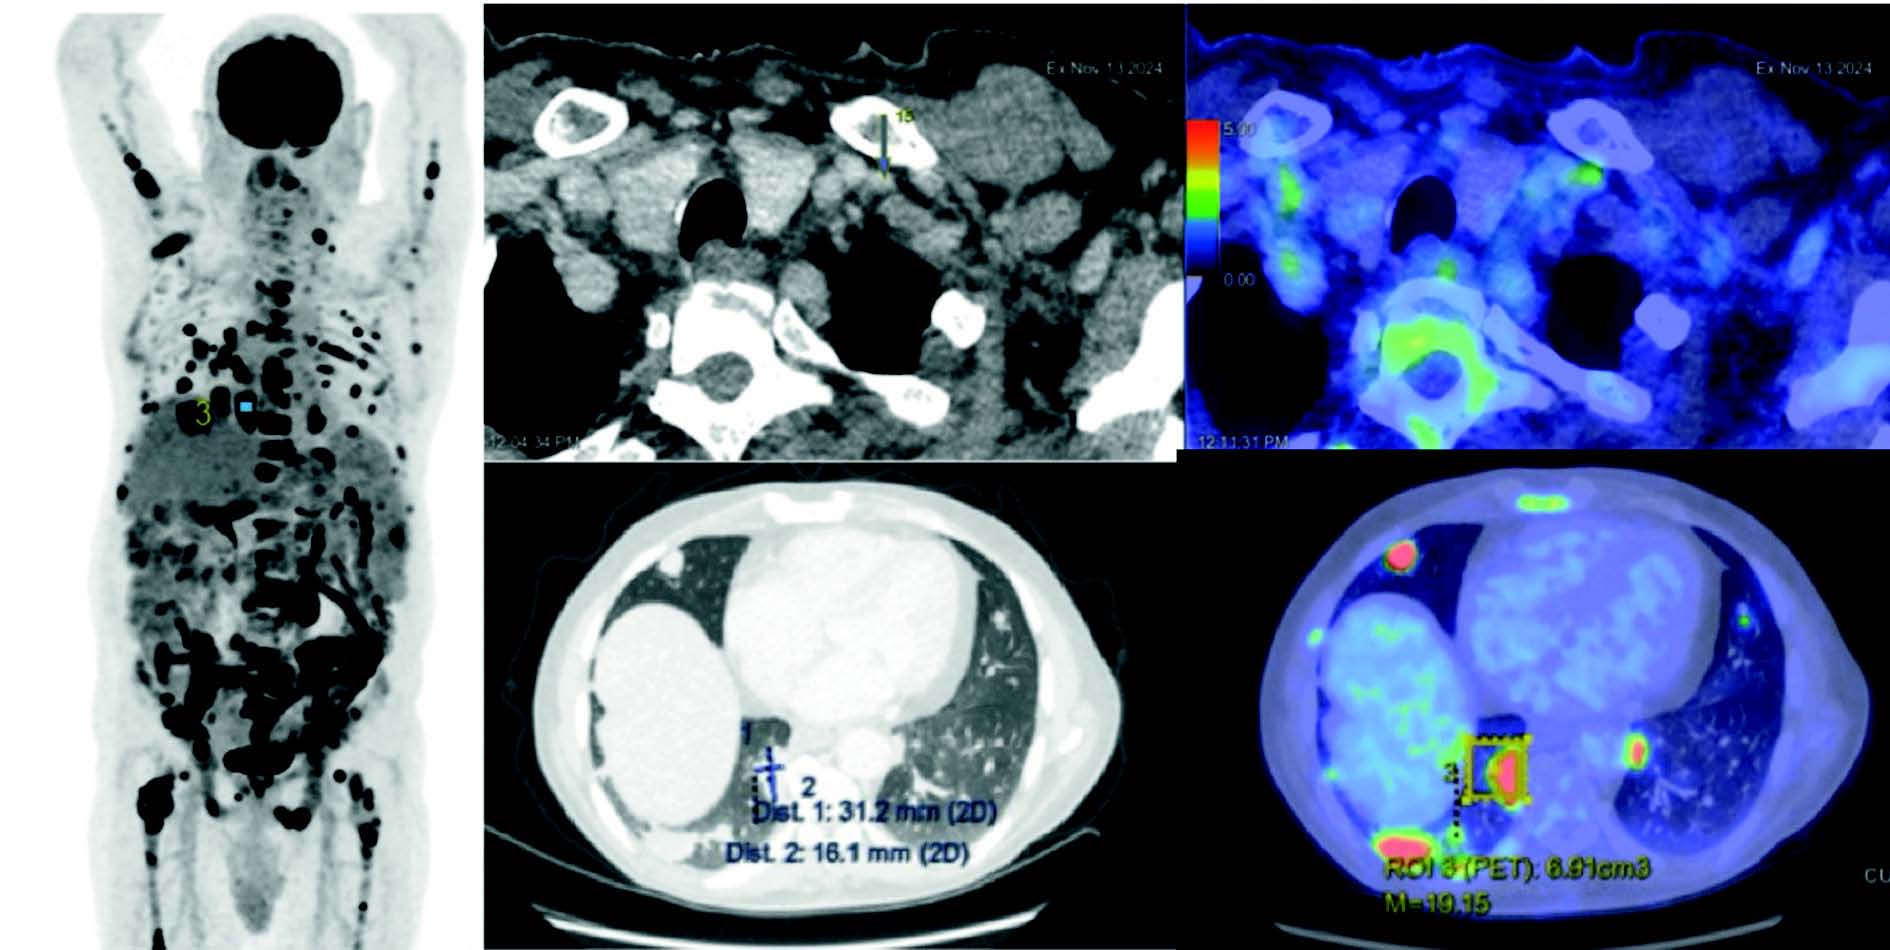

Un patient de 45 ans se présente en consultation chez son médecin traitant pour une altération de l'état général. Celui-ci lui prescrit un scanner, qui met en évidence un nodule pulmonaire, ainsi que des adénopathies et des lésions osseuses. Dans l'hypothèse d'une néoplasie pulmonaire, une microbiopsie est réalisée lors d'une fibroscopie bronchique. Celle-ci retrouve une prolifération lymphocytaire évocatrice de lymphome mais ne permet pas de poser formellement un diagnostic, en raison de sa très petite taille. Hématologue, vous recevez en consultation ce patient pour décider de la suite de la prise en charge. Afin de confirmer votre suspicion clinique, il est nécessaire d'obtenir une nouvelle preuve histologique. Au-delà de l'accessibilité, le choix de la cible doit passer par la réalisation d'un PET scanner, afin d'analyser un ganglion le plus hypermétabolique possible, pour ne pas manquer le lymphome le plus agressif (Figure 1).

Le PET-TDM retrouve une SUV importante au niveau pulmonaire, et plus faible dans les cibles ganglionnaires (Figure 3). Votre patient bénéficie d'une exérèse d'un ganglion cervical. Ce prélèvement est envoyé au laboratoire d'anatomopathologie, où, si sa taille le permet, sera partiellement congelé et le reste fixé en formol. Bien qu'on puisse réaliser la quasi-totalité des techniques sur du tissu fixé (FISH, panel NGS), les tissus congelés sont préférés pour garantir une qualité optimale grâce à une moindre dégradation des acides nucléiques.

Figure 3 PET-TDM du patient de consultation